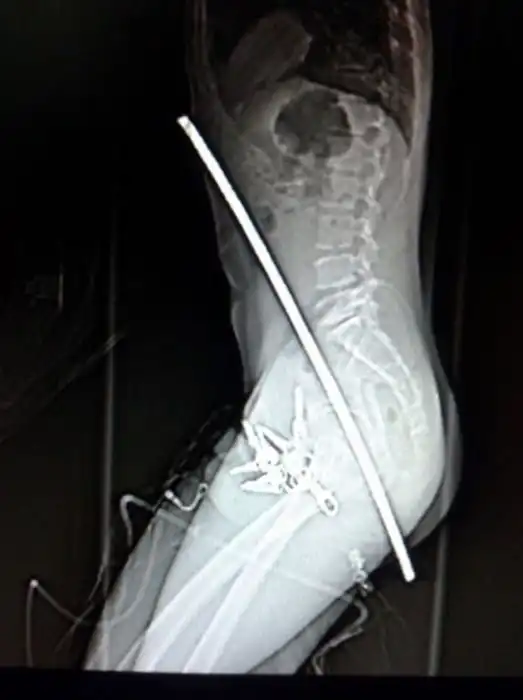

Порой даже не верится, с какими странными и необычными повреждениями в травматологию могут поступить пострадавшие. Всю эпичность профессии врачей травматологии могут с легкостью подтвердить рентгеновские снимки.

Жуткие рентгеновские снимки